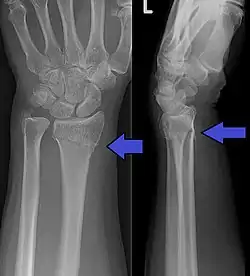

كسر كولِس (بالإنجليزية: Colles' fracture) هو كسر في النهاية البعيدة للكعبرة مع انزياح ظهري (خلفي) للمعصم واليد. يدعى هذا الكسر أحياناً بتشوه ظهر الشوكة أو تشوه الحربة بسبب الشكل الذي يأخذه مقدم الساعد. لمناقشة تفصيلية أكثر راجع كسر الكعبرة البعيد.

صورة شعاعية تظهر كسر كولس

- الميلان الظهري.

- قصر الكعبرة.

- خسارة الانحراف الزندي

- التزوي الكعبري للمعصم.

- الخلع الظهري لشدفة التفتت البعيدة في موقع الكسر

- كسر مرافق في الناتئ الإبري للزند في أكثر من 60% من الحالات.